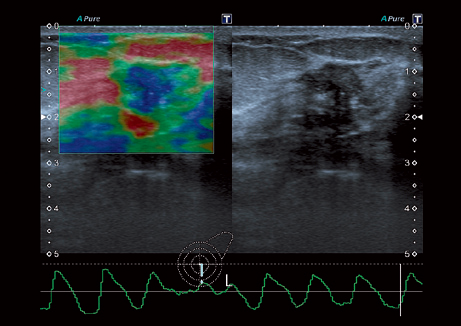

• ApliPure - технология повышения качества изображения

• Эластография

• VRI - распознавание кровотока и тканевой перфузии